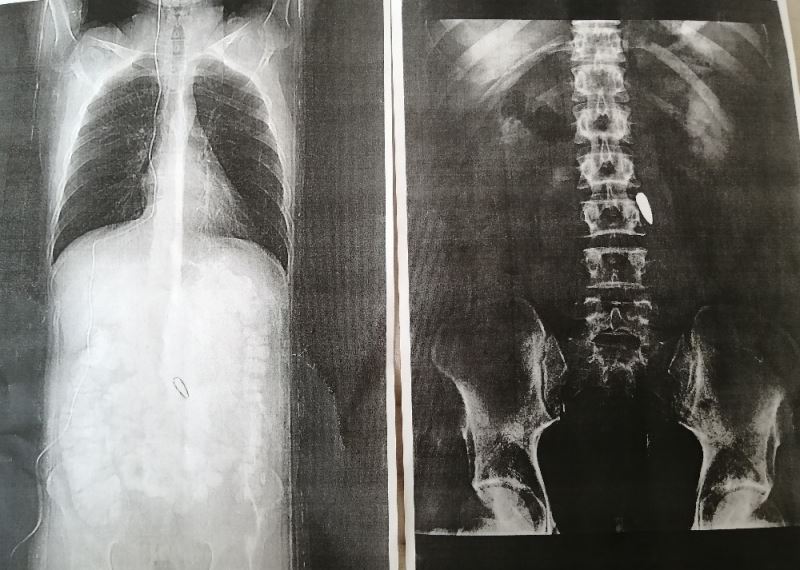

Fetullahçı Terör Örgütü (FETÖ) mensuplarının, 15 Temmuz 2016 tarihinde kalkıştığı darbe girişi sırasında, İstanbul’daki 15 Temmuz Şehitler Köprüsü’nde darbeci askerlerin sıktığı kurşunla belinden vurulan 28 yaşındaki Mersinli Gazi Onur Can Kuş, 4 yıldır yüksek hayati risk nedeniyle çıkarılamayan ve omuriliğinin hemen yanına saplanan kurşunla yaşıyor.

Hain darbe girişiminin yaşandığı 15 Temmuz 2016 tarihinde İstanbul’da özel bir şirkette çalışan ve ağabeyi Kerim Kuş ile birlikte yaşayan Onur Can Kuş, Türk Silahlı Kuvvetleri’ne sızmış FETÖ terör örgütü mensuplarının gerçekleştirdiği kalkışma sırasında, Cumhurbaşkanı Recep Tayyip Erdoğan’ın çağrısıyla darbecilere karşı koymak için sokağa çıktı. Ağabeyi ile birlikte şimdiki adı 15 Temmuz Şehitler Köprüsü olan Boğaziçi Köprüsüne giden Onur Can Kuş, orada bulunan binlerce insan gibi vatanı için bedenini hainlerin tankına ve tüfeğine siper etti. Onur Can Kuş, bu sırada hainlerin ateşlediği bir merminin beline isabet etmesi sonucu yaralandı. Yaralanan genç, orada bulunan sivil bir vatandaşın motosikletiyle Haydarpaşa Numune Eğitim ve Araştırma Hastanesi’ne kaldırıldı. Kuş, burada hemen ameliyata alınırken, omuriliğinin hemen yanına saplanan kurşun, yüksek hayati risk nedeniyle çıkarılamadı.

Bölgede büyük bir kaos yaşandığını ve bulunduğu yerde ne bir ambulans ne de bir araç olmadığını söyleyen Onur Can Kuş, orada bulunan sivil bir şahıs tarafından motosikletle Haydarpaşa Numune Eğitim ve Araştırma Hastanesi’ne götürülerek ameliyata alındığını belirtti. Kurşunun hala vücudunda olduğunu ameliyattan 3 gün sonra öğrendiğini ifade eden Kuş, "Kurşun hala içimde. Yüksek hayati risk olduğu için çıkarmamışlar. Vücut, kurşunu yağ tabakası ile çevrelemiş. Şu an için bana her hangi bir sıkıntı vermiyor. Mersin’e geldikten sonra da kontrole gittim. Mersin Şehir Hastanesi’nde de kurşunun çıkarılmasının riskli olduğunu söylediler, o yüzden hayatımı bu şekilde idame ettiriyorum. Kurşunun vücudumda olması sağlığımı etkilemiyor ama ağır sporlar yapmamaya dikkat ediyorum" diye konuştu.